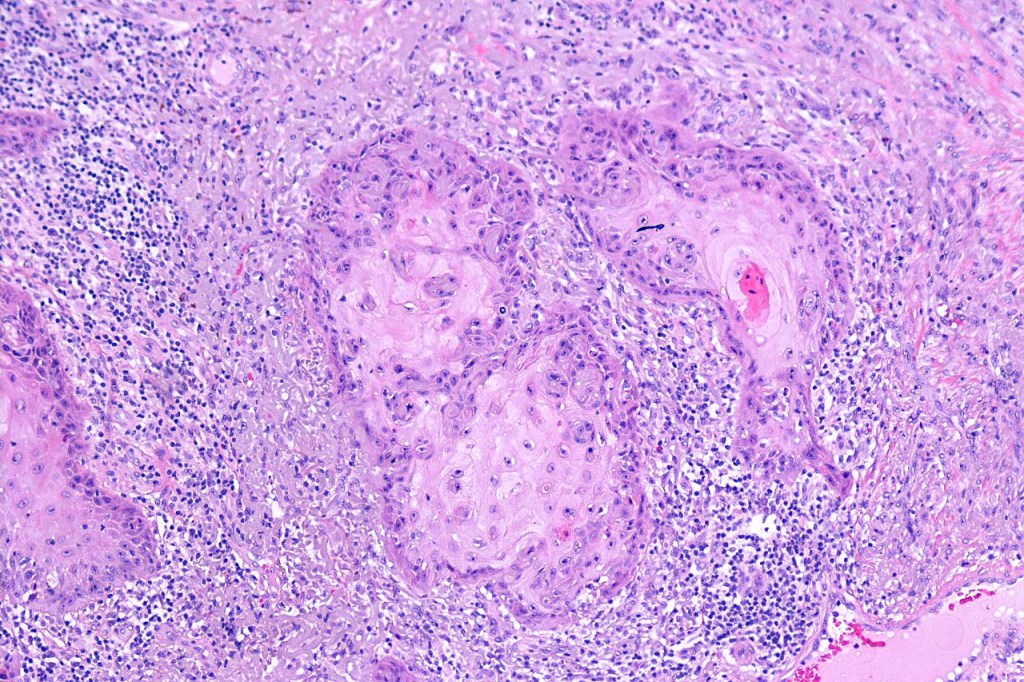

•Well differentiated squamous epithelium often with a characteristic ground-glass appearance

•Only mild pleomorphism & basally located mitoses

•Neutrophil-rich microabscesses & necrosis

Below is a fascinating case shared on McKee Derm by Dr. James Simpson. There is an obvious keratoacanthoma but at the edge of the lesion there is marked atypia with nuclear enlargement and pleomorphism. This is also evident in the adjacent epidermis and in the deeper nests.